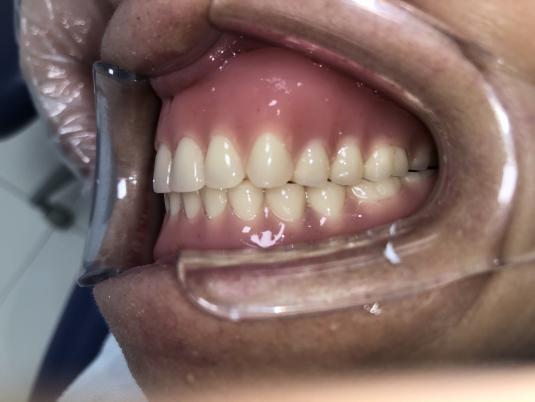

62岁深圳老人:这法子整出来的“假牙” 又稳又好用!

近日,博爱曙光口腔科又完成一例BPS全口吸附性义齿修复。